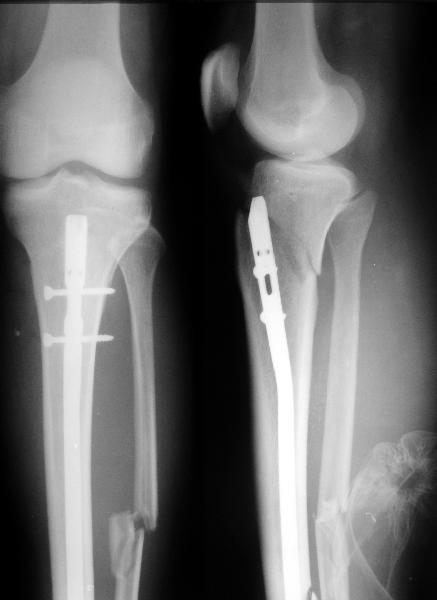

I applied a simple Ilizarov frame, and after reduction inserted a locking screw into a 45 degree hole and two AP screws "miss a nail".

X-rays attached.

Кликните для загрузки файла get_image.jpg

Так и сделали. Плюс винт в 45 градусное отверстие и два в передне-заднем направлении. Снимок в приложении выше.